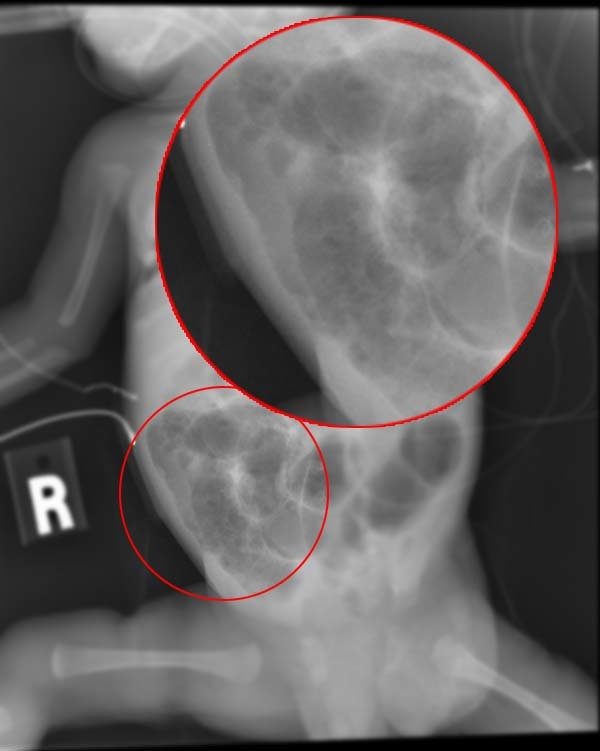

Wat is Dit?

Symptomen

• Braken

• Diarree

• Rectaal bloedverlies

• Abdominale distensie

NEC

Enterocolitis

1 tot 3 per 1000 levendgeborenen

Braken, diarree

Rectaal bloedverlies

Abdominale distensie

Behandeling

Chirurgie, antibiotica

Sources: UpToDateClinical features and diagnosis of necrotizing enterocolitis in newborns